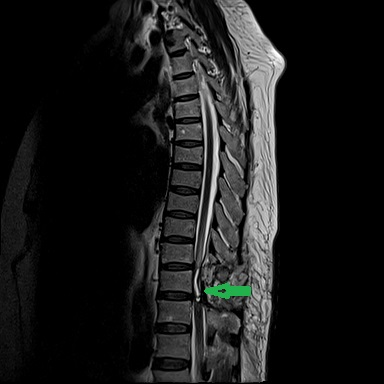

患者康婆婆(化名)今年已近70岁,因“右下肢麻木5+月加重伴疼痛3+月”前来医院治疗,行腰部核磁检查发现胸11椎体平面脊髓内囊性占位,考虑室管膜瘤的肿瘤性病变。患者下肢长期麻木伴疼痛,经神经外科医疗团队研究讨论,为患者行了微创的胸椎椎管骨质切开和脊髓内肿瘤病变的切除手术治疗,切除了患者的肿瘤后,患者下肢肌力和麻木感明显改善。

手术前检查